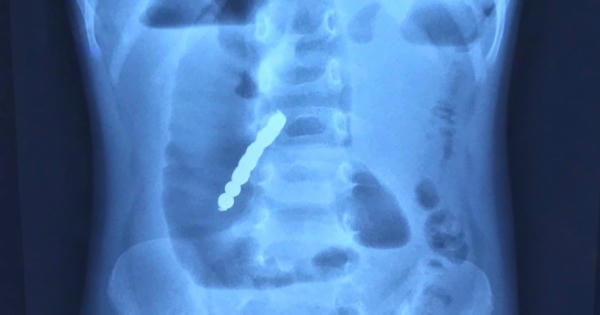

Ngày 4/3, trẻ nhập viện trong tình trạng đau bụng, nôn nhiều. Kết quả chụp X-quang phát hiện hình ảnh tắc ruột kèm dị vật cản quang trong ổ bụng là 7 khối hình cầu dính thành chuỗi.